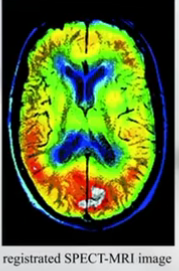

六、可视化(Visualization)

-Color overlay(彩色叠加,实现差异的变化)